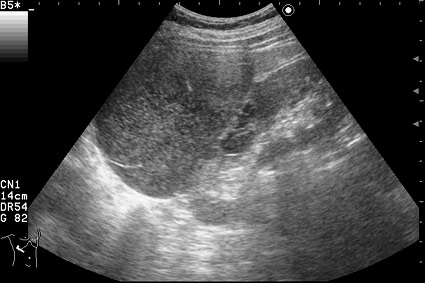

Периодически беспокоят несильные боли справа, чувство дискомфорта.

Сонограмма правой почки.

Нет, это кистоподобное образование, связанное с почкой.

Необычнвя картинка. В голову приходят самые "сумашедшие" предположения (в т.ч. малигнизация кисты, но нет кровотока, нагноившаяся киста, но нет реакции ее стенки; киста с густым содержимым, но отчего оно так загустело?). Просветите нас, пожалуйста.

Почечно-клеточный рак правой почки, кистозная форма.

Но только по густому содержимому кистозного компонента. Стенка тонкая, кровоток не прокрашивается (единичный мелкий срез сосуда в центре образования больше похож на артефакт, а м.б. им и является).

Если бы в этом случае и содержимое было бы более "жидким", вероятность постановки правильного диагноза была бы минимальной.

Я в своем заключении предположил кисту с внутренним кровоизлиянием.

И ошибся.